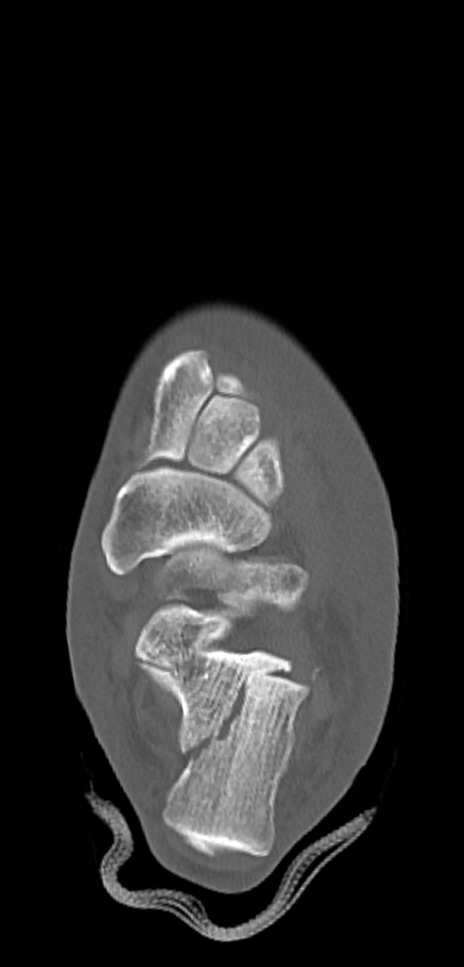

左足関節CT

冠状断像